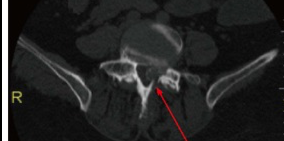

World J Orthop. 2016 Nov 18;7(11):766-775. Spinal Gout: A Review With Case Illustration Hossein ElgafyXiaochen LiuJoseph Herron

Abstract Aim: To summarize clinical presentations and treatment options of spinal gout in the literature from 2000 to 2014, and present theories for possible mechanism of spinal gout formation. Methods: The authors reviewed 68 published cases of spinal gout, which were collected by searching "spinal gout" on PubMed from 2000 to 2014. The data were analyzed for clinical features, anatomical location of spinal gout, laboratory studies, imaging studies, and treatment choices. Results: Of the 68 patients reviewed, the most common clinical presentation was back or neck pain in 69.1% of patients. The most common lab

oratory study was elevated uric acid levels in 66.2% of patients. The most common diagnostic image finding was hypointense lesion of the gout tophi on the T1-weighted magnetic resonance imaging scan. The most common surgical treatment performed was a laminectomy in 51.5% and non-surgical treatment was performed in 29.4% of patients. Conclusion: Spinal gout most commonly present as back or neck pain with majority of reported patients with elevated uric acid. The diagnosis of spinal gout is confirmed with the presence of negatively birefringent monosodium urate crystals in tissue. Treatment for spinal gout involves medication for the reduction of uric acid level and surgery if patient symptoms failed to respond to medical treatment.